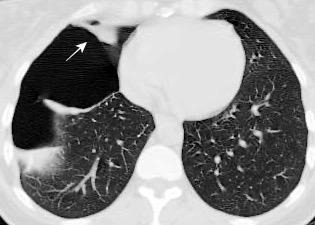

Signos radiológicos TC

Hallifax RJ et al. State-of-the-art: Radiological investigation of pleural disease Respiratory Medicine 2017

Nivel hidroaéreo o burbujas

Forma lenticular o elíptica Ángulos obtusos

> Grasa Extrapleural (60-80%)

Situación no gravitacional (no siempre)

Compresión de estructuras pulmonares

Límite muy bien definido Tabicación

Engrosamiento de la pleura parietal 36/ 59 exudados (61%) 56% de D. paraneumónicos 100% de empiemas Especificidad.. 96%.

Exudado versus trasudado.

Aquino SL, et al. Pleural exudates and transudates: diagnosis with contrast-enhanced CT. Radiology 1994

Signo de la Pleura separada “Split pleural sign”

Capas pleurales de grosor uniforme realzadas por el contraste

No específico de empiema. Indica “exudado”. 68% de pacientes con empiema pleural.

Capas pleurales de grosor uniforme

Realce grasa extrapleural (30%)

> Grasa Extrapleural. (60-80%)

Kraus GJ. Split pleural sign. Radiology 2007